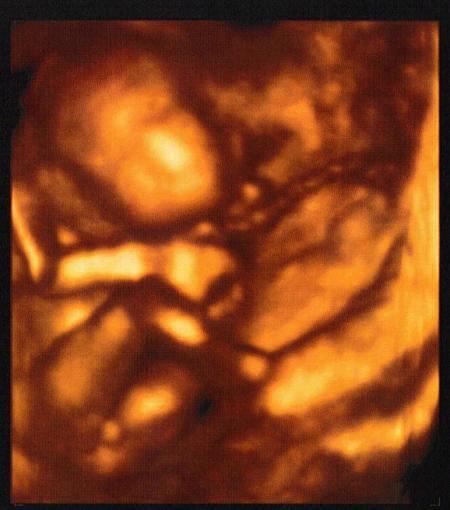

Jaa...wir bekommen auch einen Jungen Hatte ich ja auch schon vermutet, denn bei mir sind die Schwangerschaften mit den Mädels so gaaanz anders als die mit den Jungs. Freut mich, das es die soweit gut geht. Der Termin wird sicher sehr spannend. Man soll da ja doch viel mehr erfahren , als beim Arzt. Ich kenne das nicht, war noch nie da... Aber mein Arzt nimmt sich auch so immer ganz viel Zeit und macht ja auch jedesmal US. Auch 4D, das ist immer klasse. Hier nochmal mein kleiner.... LG

Bild zu